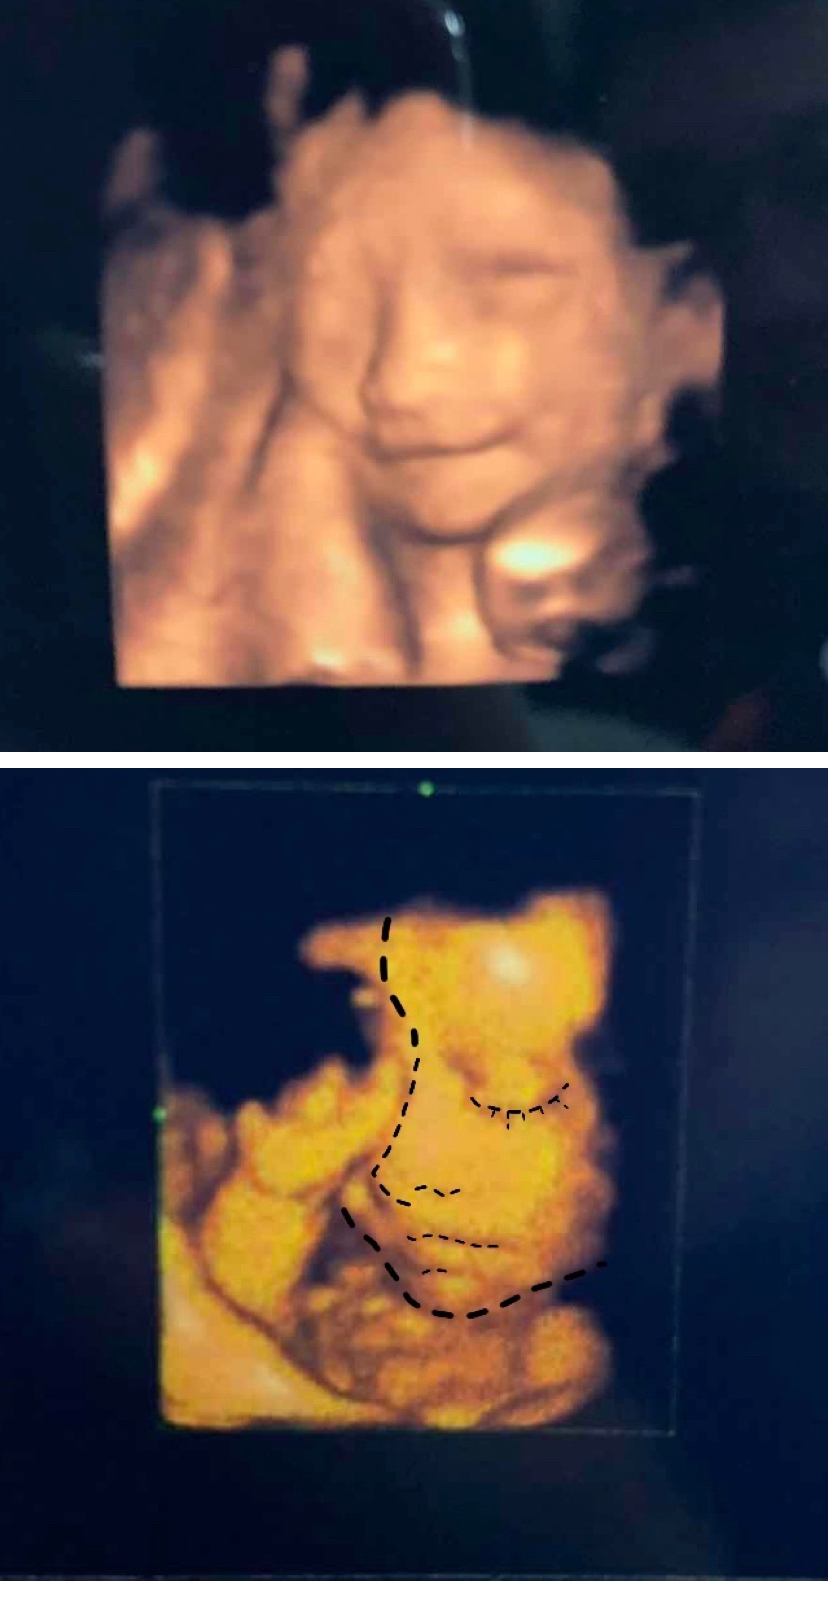

孕30周+6天

好漂亮的宝宝~

宝宝还笑着呢。